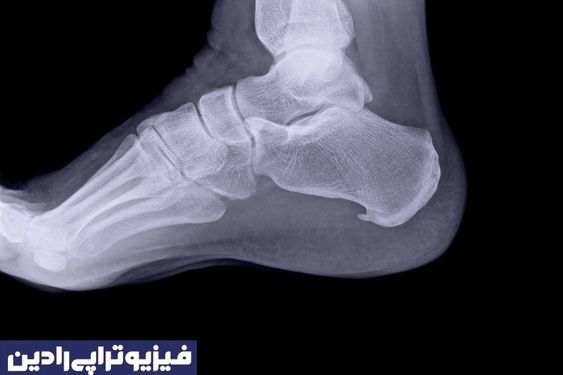

بعضی مواقع این امکان وجود دارد که این عارضه از زیر پاشنه تا قوس پا گسترش پیدا کند که به این ناحیه «فاسیای کف پا» گفته میشود. زمانی که خار پاشنه در اشعه ایکس دیده میشود، ممکن است طول آن تا یک و نیم سانتی متر برسد.